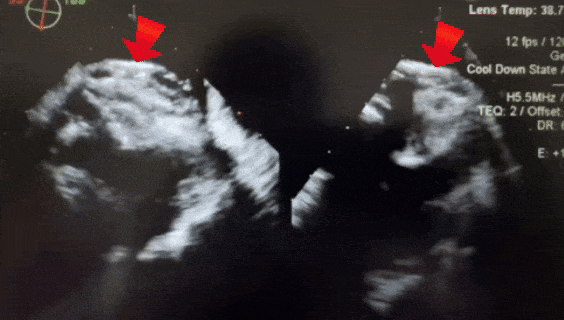

释放后超声

释放封堵器后,封堵器盘面稳固贴壁,成型良好,超声下未见分流,封堵成功。

四腔心切面下观察封堵器,左右盘面稳固贴壁,盘面平整,未影响瓣膜结构

主动脉短轴切面下观察封堵器,封堵器形态稳定,无残余分流